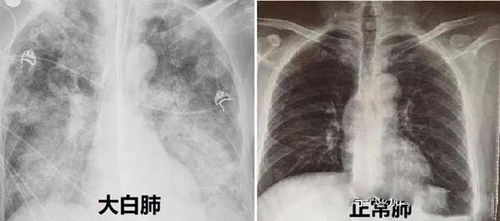

到了医院,医生迅速为我进行了检查。经过一系列的检测,确诊我感染了甲型流感病毒。更糟糕的是,我的肺部X光片显示已经出现了炎症,初步诊断为病毒性肺炎。听到这个结果时,我心里一阵发凉。原本以为只是普通的流感,没想到竟会发展成这么严重的状况。